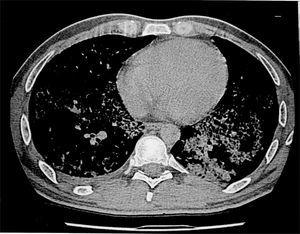

En la analítica de ingreso destaca una presión arterial de oxígeno (PaO2) basal de 63 mmHg; velocidad de sedimentación globular: 92 mm/h; recuento de leucocitos de 9.300 l/mm3 (73% neutrófilos); lacticodeshidrogenasa (LDH): 957 mg/dl, y fibrinógeno: 954 mg/dl. En la radiografía de tórax se observa infiltrado intersticio-alveolar difuso bilateral sobre el parénquima pulmonar. En la TAC torácica se observa una gran afectación del parénquima pulmonar con áreas de afectación alveolar, zonas simétricas y bilaterales de opacidad en vidrio deslustrado y adenopatías en hilio pulmonar, paratraqueales y por debajo de la carina (fig. 1). Al paciente se le realizó una biopsia transbronquial que fue inespecífica. Se le realizó una biopsia pulmonar en quirófano que muestra en el estudio histológico que se trata de una proteinosis alveolar. El estudio microbiológico de la biopsia aisla una Nocardia sp. Quince días después del ingreso el paciente presenta empeoramiento clínico con gran aumento de la disnea, hipoxia y empeoramiento del gradiente alveolo-arterial. Dada la situación clínica se decide realizarle un lavado broncoalveolar bilateral.

Figura 1. Imagen de la tomografía axial computarizada (TAC) torácica en donde se observa la afectación pulmonar del paciente antes de realizar el lavado broncoalveolar. En ella se aprecia una mayor afectación del pulmón izquierdo; ésa es la razón por la que el lavado se inicia por este pulmón.